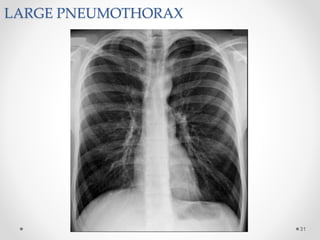

LARGE PNEUMOTHORAX

Radiological manifestations of large pneumothorax

• Mediastinal shift,

• Flattening of the hemidiaphragm &

• Lung collapse.